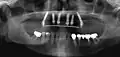

Les techniques d'implant permettent de remplacer la ou les dent(s) manquante(s) de manière très satisfaisante, autant sur le plan esthétique que fonctionnel. L'ancien dogme « une dent remplacée = un implant » est dépassé. Pour des raisons de coûts mais aussi à la suite de progrès techniques (métallurgie, radiographie, techniques de fabrication en laboratoires de prothèses, techniques opératoires), il est possible de réaliser par exemple une prothèse fixe de douze dents sur six implants.

Prothèses fixes sur implants

Il en existe de nombreux types adaptés à chaque cas particulier: couronnes unitaires scellées ou vissées, bridges scellés ou vissés, prothèses totales résines ou céramiques vissées, bridge complet étendu à la totalité de l'arcade dentaire .

Prothèse totales fixes sur implants

Elles ont en règle réalisables sur six implants (selon des modalités bien précises pour l'observation desquelles le poseur d'implant doit avoir les qualifications requises). Selon la récession osseuse du patient à la suite de la perte de ses dents, on réalisera une prothèse sans ou avec fausse gencive. Moins coûteuses que les bridges, ces prothèses sont moins longues à réaliser. Rien n'empêche cependant le patient de faire remplacer sa prothèse résine par une prothèse céramique après une période d'observation de deux ans.